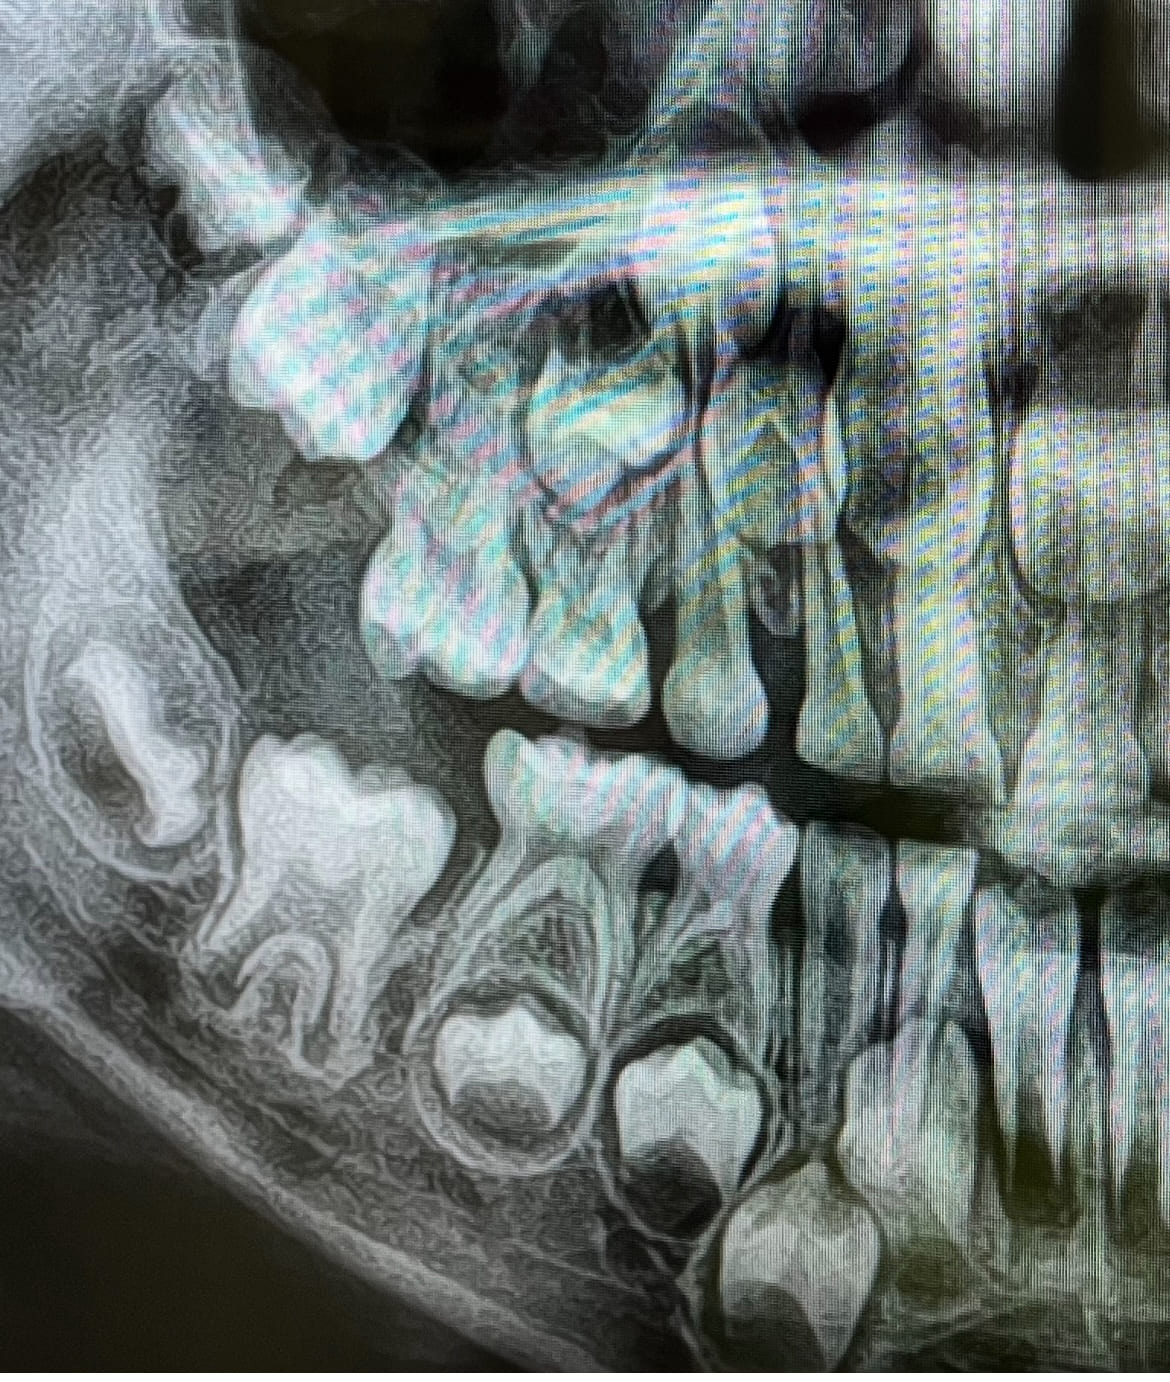

5歳0ヶ月の男児です

先月下顎のAAが生え変わったのを機にパノラマを撮影してもらいましたが

上顎の両側の5番が写っていませんでした

円のようなものは見えるのですが、今後歯が萌えてくる可能性はありますでしょうか

5番は先天性欠損も多いとこのことでその可能性が高いのか…

写真を添付いたします。よろしくお願いいたします

5歳であれば5番の歯冠部のエナメル質が出来始めている時期だと思います。ですからレントゲンに写ってきて当然だと思います。

ただ「円のようなものは見える」の円はなんでしょうね?

ただ円が写っていたのでもしかしたら萌えてくるかも…との思いでいます

添付していただいたレントゲンにはかすかに歯胚らしきものが写っていいるようにも見えます、しかしこれが永久歯なのかどうかこのレントゲンでは確定できません。

半年くらい先にレントゲンを取れば判断できると思います、それまでお待ちになってください。